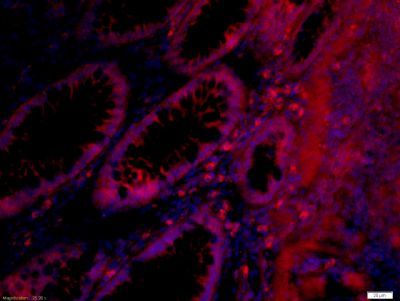

CELSR3 Rabbit Polyclonal Antibody

ELISA, ICC, IF, IHC-Fr, IHC-P

应用稀释比例:IHC-P=1:100-500, IHC-F=1:100-500, ICC/IF=1:100-500, IF=1:100-500, ELISA=1:5000-10000